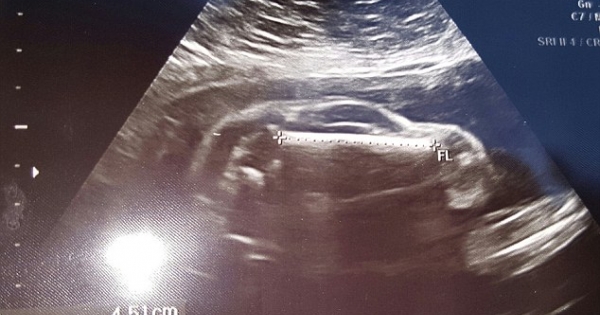

超音波照片真的很千变万化!

第一次看到宝宝的超音波照片,準父母们一定会很激动。但不久前,国外一名网友带妻子去做检查时,却看到了惊人的一幕。超音波检查照片中显示的不是胎儿…